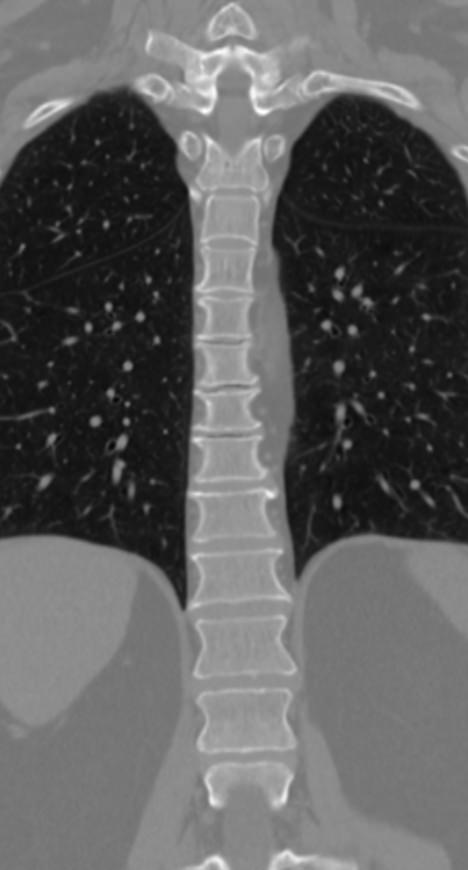

Мультиспиральная компьютерная томография является одним из наиболее информативных методов диагностики дегенеративно-дистрофических заболеваний, травматических, воспалительных изменений, а также опухолевых процессов позвоночника. Методика предусматривает использование рентгеновского излучения для получения детализированных снимков костных структур позвоночника, межпозвонковых суставов и межпозвоночных дисков.

При подозрении на распространенный процесс с поражением различных уровней позвоночного столба показано проведение мультиспиральной КТ трех отделов позвоночника.

В клинике «Доступная медицина» установлены современные мультиспиральные компьютерные томографы экспертного класса TOSHIBA AQUILION в различных модификациях (64-срезовый и 128-срезовый), на которых выполняются комплексные обследования позвоночника, включая одномоментное исследование несколько отделов. Аппараты производят сканирование с помощью рентгеновских лучей, делая тончайшие срезы с шагом от 0,5 мм, затем с помощью компьютерных программ полученные данные преобразуются в изображения трехмерного формата, что обеспечивает точность и достоверность диагностики.

Что покажет КТ трех отделов позвоночника

С помощью мультиспиральной КТ можно диагностировать:

- патологические изгибы позвоночника, сколиоз, усиленный или выпрямленный лордоз как нарушение статической функции позвоночника;